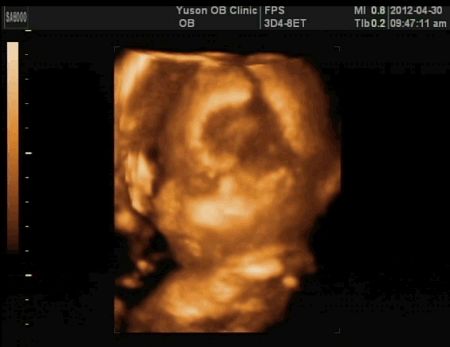

今天醫生拍了很多4D超音波給我看,哈哈!

我發現我兒子很愛做這種沉思的表情

每次照超音波他都會來一個這樣的破似,不過醫生還是又猛搖我的肚子一陣,要他換個姿勢再來一次!